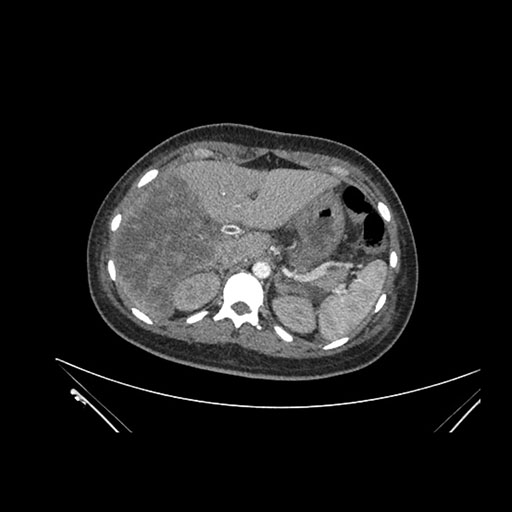

Imaging Analysis

Look through the patient's CT scan to identify any areas of concern for the necessary procedure.

Axial Arterial

Based on initial findings, which issue(s) would you be most concerned about?